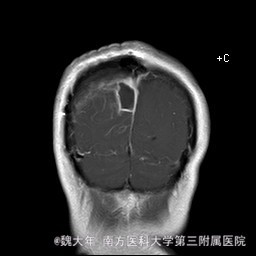

52岁,女性,因“反复头痛10余年,加重1年”入院。患者10余年前无明显诱因始出现头痛,表现为全头发作性胀痛,反复发作,无伴头晕、恶心,无呕吐、肢体抽搐,自行服药(具体不详)及休息后缓解,未予特殊处理。1年前患者觉头痛逐渐加重,以右顶部为甚,劳累或日晒后加重,无头晕、视物旋转,无恶心、呕吐,无发热、寒战,休息或平躺后症状稍有缓解,自行服药不能改善,至当地医院就诊,查颅脑MRI和CT提示“右侧顶部脑膜瘤”。

行“右顶开颅右顶部矢状窦旁脑膜瘤切除术”。取右顶马蹄形手术切口 ,颞侧翻开皮瓣,电刀切开骨膜,中线矢状缝上前、后极各钻一孔,颞侧后方钻一孔,铣刀铣一长方形(7*6cm)骨瓣,见硬膜表面较多点状渗血,予充分止血,悬吊硬膜。 显微镜下切除肿瘤:沿肿瘤边缘剪开硬膜后,见一大小约5*5*6cm肿瘤,沿硬膜内侧面呈匍匐状生长,边界与脑组织有蛛网膜分隔,质地较韧,基底与矢状窦关系密切,靠内侧与大脑镰粘连紧密,血供丰富。仔细分离肿瘤与脑组织的粘连,全切除肿瘤。肿瘤基底与矢窦粘连紧密,并破坏矢状窦侧壁,予低功率电刀反复烧灼,直至肿瘤无明显血供表现。严密止血后常规关颅。

术后1周复查头颅MR未见明显肿瘤残留,拆线后出院。